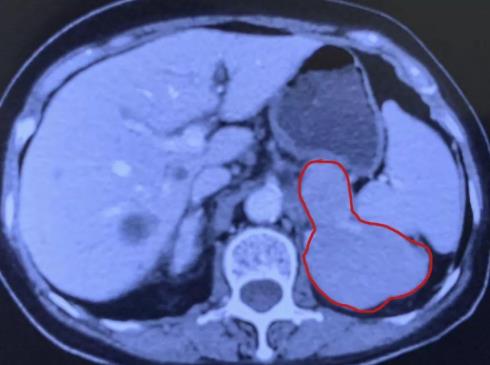

廣州復大腫瘤醫院的冷凍專家團隊立刻組織了會診,他們評價狀況:此次病情跟十年前、三年前都不一樣,以往的腫瘤比較小,大概三公分左右,可以做到控制性的消融,但是這次的腫瘤超過了十公分,原則上,只能做一個姑息性的消融。據廣州復大腫瘤醫院副院長牛立志教授介紹,“因為考慮到老人家身體虛弱,年齡大,腫瘤大,我們考慮做一個姑息性的消融,主要是為了減輕負荷,減少疼痛。術中我們一共插了六根針,大約將90%的腫瘤做了消融!毙g后老奶奶身體正常,回到家鄉醫院調養身體。

兩個月后,李阿婆回到廣州復大腫瘤醫院進行復診。根據以往經驗,醫生們原本打算對她的病情進行第二次消融的,但經過影像學檢查,發現剩余的腫瘤基本已經完全壞死了!也就是講原本只消融了90%的腫瘤,現在連剩余的腫瘤也死亡了,老人家完全不需要做第二次消融了!這個意外的驚喜令李阿婆與家人感到特別地開心,李阿婆家人評價說:“真沒有想到廣州復大醫院竟然會有這樣的技術!”